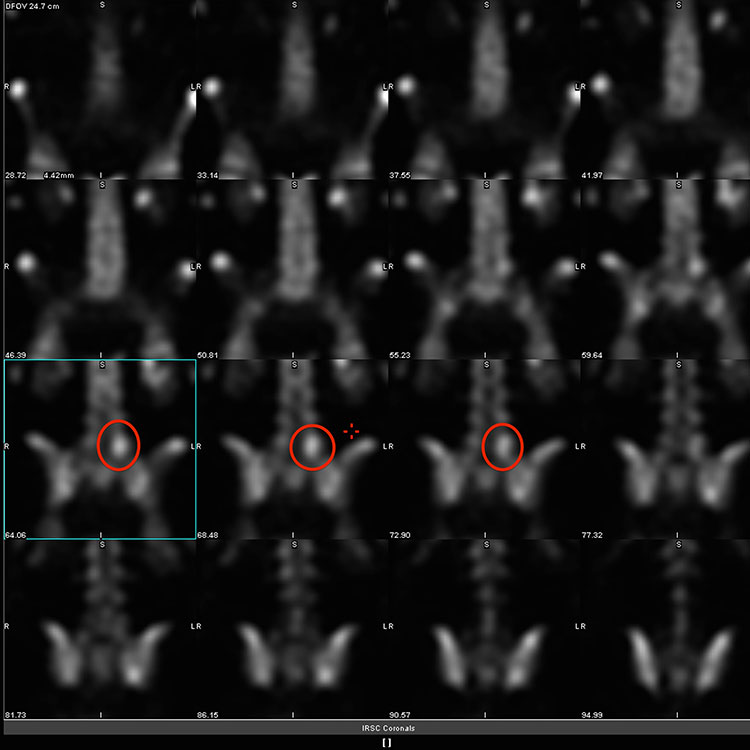

3. 골 스캔 (Bone Scan/ Scintigraphy)

• 방사선 표지 동위원소(주로 테크네튬-99/ technetium-99m) 주사를 사용.

• 증가된 골 리모델링을 감지하는 데 매우 민감하다.

• 피로골절의 임상적 회복 후에도 방사선 동위원소 흡수가 한동안 유지될 수 있으므로, 회복 모니터링에는 유용성이 떨어질 수 있다.

• 감염이나 종양과 같은 다른 원인으로도 동위원소 흡수가 증가할 수 있으므로 피로골절에 특이적이지는 않다.

• 치골 관련 통증의 경우 신티그램 scintigraphy 이 치골 결합 주변의 신호 증가를 보여줄 수 있다.

• 대퇴골 피로골절을 진단을 확인하고 손상범위를 파악하는데 사용된다.